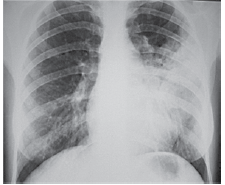

Mulher de 49 anos é internada devido dispneia, febre e dor torácica à esquerda iniciados há 3 dias. Pressão arterial: 110 x 60 mmHg, pulso: 115 bpm; temperatura: 38,3 ºC, frequência respiratória: 26 ipm e saturação arterial de oxigênio: 85%. Radiografia realizada é ilustrada a seguir.

Nesse momento, é correto afirmar: